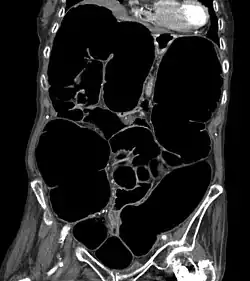

![]() Obraz pseudoniedrożności w badaniu CT | |

Zespół Ogilviego (ang. Ogilvie syndrome), ostra pseudoniedrożność okrężnicy (acute colonic pseudo-obstruction) – zespół objawów związanych z ostrym rozdęciem jelita grubego przy braku mechanicznej przeszkody powodującej jego niedrożność.

Rozpoznanie zespołu Ogilviego jest trudne i często opóźnione[1] ze względu na podobieństwo objawów do niedrożności mechanicznej i bardzo częste współistnienie innych, ciężkich chorób pacjenta. Podstawą rozpoznania jest stwierdzenie typowych objawów klinicznych oraz badanie radiologiczne (zdjęcie przeglądowe) wykazujące poszerzenie okrężnicy, często z poziomami płynów. Przy ocenie badania radiologicznego istotne znaczenie ma pomiar szerokości kątnicy ze względu na wybór sposobu dalszego postępowania i znaczenie rokownicze[9].

W rozpoznaniu różnicowym uwzględnia się niedrożność mechaniczną oraz ostre rozdęcie okrężnicy w przebiegu jej zapalenia rzekomobłoniastego. W przypadku wątpliwości co do przyczyny rozdęcia okrężnicy pomocne może być wykonanie badania tomograficznego lub sigmoidoskopii. Przy ocenie badań zwraca się szczególną uwagę na obecność objawów najgroźniejszych powikłań zespołu Ogilviego, jakimi są niedokrwienie jelita i jego perforacja.